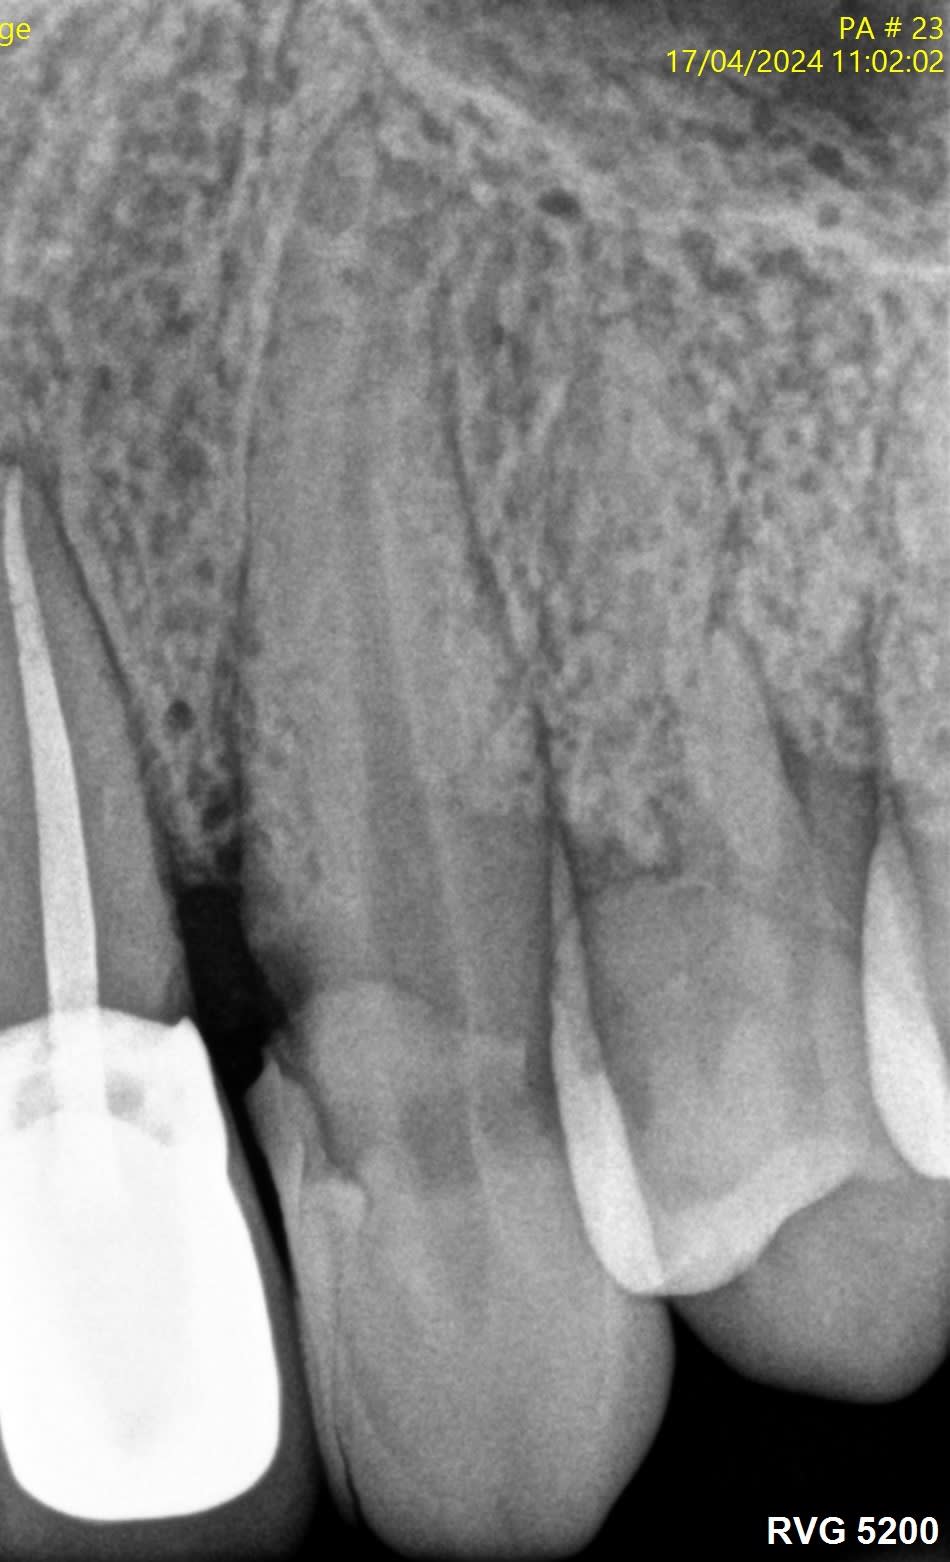

Voici quelques radio pour illustrer...

J’ai l’impression que sur les radios que tu montres il y a des fractures verticales.

La 24 et la 25, t'aurais carrément dû les virer...

> La 24 et la 25, t'aurais carrément dû les virer...

Du tout, c'est joli la zircone, et c'est gratuit.

Sur des endo avec une pulpe saine comme les 24 25, en t'arrêtant à 5 mm, tu auras le même taux de réussite qu'à 0.